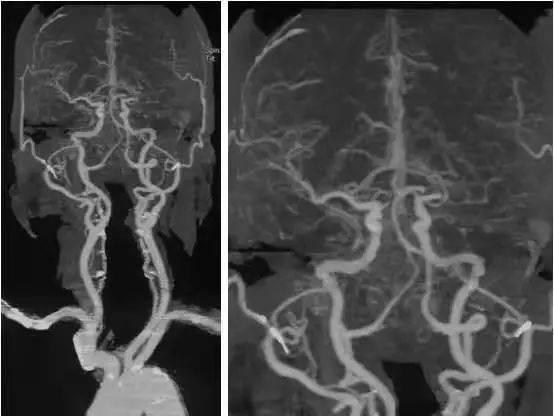

MS的 MRI特點(diǎn)。

側(cè)腦室周圍、半卵圓中心、胼胝體與腦室間可見類圓形或融合性斑塊, T1W I低信號 、T2WI高信號,大小不一,常見于側(cè)腦室前角和后角周圍,大融合性斑塊多累及側(cè)腦室體部, 腦干、小腦、脊髓可見不規(guī)則斑塊。 MS患者病程較長可伴腦室系統(tǒng)擴(kuò)張、腦溝增寬等腦白質(zhì)萎縮征象。

T2W I顯示大腦白質(zhì)MS斑塊較好, 質(zhì)子密度加權(quán)像顯示腦干和小腦斑塊較清晰,T1W I可鑒別MS陳舊與新鮮斑塊,前 者 T1W I呈明顯低信號,注 射 Gd-DTPA后不強(qiáng)化,后者呈模糊等信號,有顯著強(qiáng)化效應(yīng)。 MRI診斷顱內(nèi)多發(fā)性脫髓鞘病變注意事項(xiàng)。

MRI在臨床的廣泛應(yīng)用發(fā)現(xiàn)許多顱內(nèi)多發(fā)性病變, 腫瘤、腦梗死、寄生蟲病等??纱_診, 許多原因不明的顱內(nèi)多發(fā)性病變往往根據(jù)其形態(tài)及分布范圍被歸為“脫髓鞘”病變,導(dǎo)致對脫髓鞘及脫髓鞘疾病概念認(rèn)識的混亂。 腦室旁T2W I高信號可見于多種病理過程,甚至正常的老年人,但老年人改變常較輕微, T2W I顯示數(shù)個(gè)不對稱的界限清楚、緊鄰腦室表面病灶常提示MS, 與纖維束走行一致的放射性分布的脫髓鞘區(qū)更有診斷意義,急性期病灶有增強(qiáng)效應(yīng)。

顱內(nèi)多發(fā)性脫髓鞘病變典型地見于多發(fā)性硬化患者, CNS脫髓鞘病變是自身免疫機(jī)制導(dǎo)致。然而,多種神經(jīng)系統(tǒng)病變?nèi)缪h(huán)障礙、中毒、感染、變性及營養(yǎng)障礙等均可導(dǎo)致脫髓鞘或類似脫髓鞘病變,是廣義的脫髓鞘疾病,后者應(yīng)根據(jù)患者的臨床表現(xiàn)、自然病程、病變影像學(xué)特點(diǎn)及治療反應(yīng)等與MS鑒別,避 免 CNS脫髓鞘病變的臨床誤診或過度診斷。